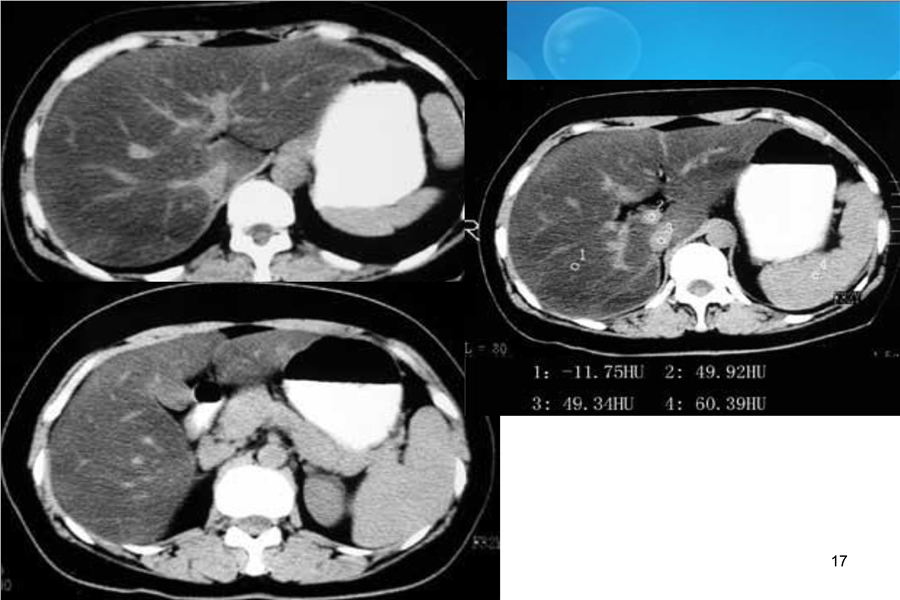

消化系统二